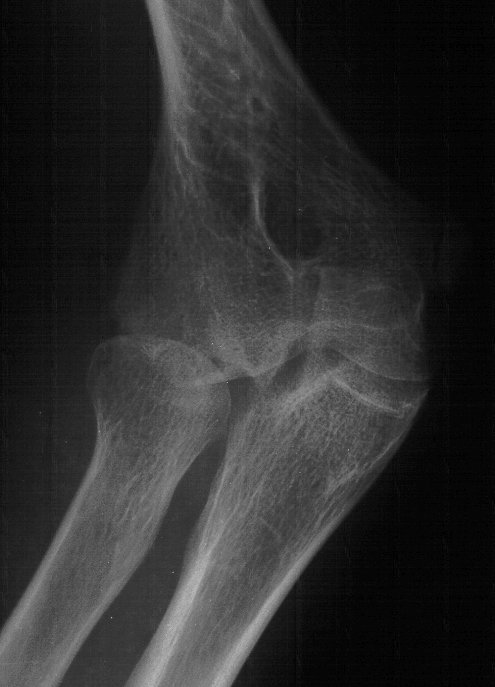

Plain films show humeral osteophytes and posttraumatic changes of the capitellum and radial head.

Click for larger image